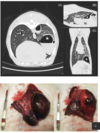

What condition is shown in this CT and gross path image series? What is the prognosis overall for the condition?

Traumatic pulmonary pseudocyst Good prognosis, majority resolve without intervention "Traumatic pulmonary pseudocysts in nine dogs and two cats" Montano et al Vet Surg 2023- 3 had surgery due pneumothorax, one euthanised due to comorbidities, rest survived with medical management